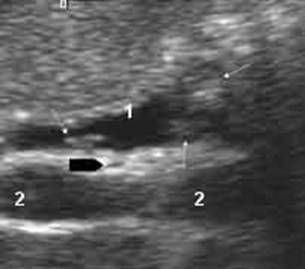

-Ecografia addominale : si tratta di una metodica di valutazione morfologica dell'albero biliare non invasiva , poco costosa e facilmente disponibile. Rappresenta il primo step nella diagnosi di pazienti con sintomi relativi al sistema biliare.Gli ultrasuoni presentano una sensibilità molto alta nell'identificazione dei calcoli della colecisti ( 97 % in situazioni di elezione e 80% in presenza di una colecistite acuta) ma presenta una sensibilità molto bassa (15-40%) nei confronti dei calcoli coledociti; questo a causa principalmente del meteorismo duodenale.Tuttavia riescono ad identificare una dilatazione dell'abero biliare con un'accuratezza del 90%.

In sintesi l'utilizzo dell'ecografia addominale per l'individuazione di coledoco litiasi garantisce un grado di precisione valutabile nel 15-20%. 21

Fig 2 esame ultrasonografico - dilatazione della via biliare principale(1)